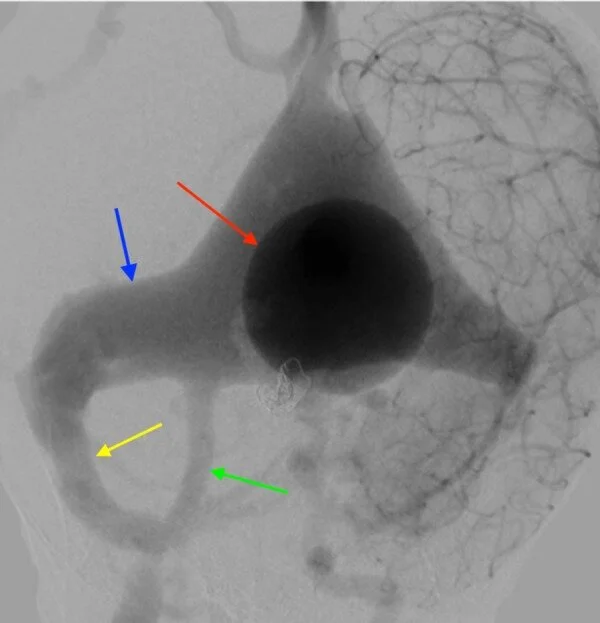

Vein of Galen aneurysmal malformation (VGAM) is a rare angiopathy, which most commonly presents in infancy. Although very rare, it is associated with high morbidity and mortality rates. In order to minimize such morbid rates, a prompt diagnosis followed by a timely initiation of management is crucial. Multiple antenatal and postnatal imaging techniques for the diagnosis have been described and discussed in the literature. However, to our knowledge, a comprehensive review exploring such a list of imaging options for VGAM has never been established. We aim to review the diagnostic tools to aid in better understanding of the investigative modalities physicians may choose from when treating patients with a VGAM.